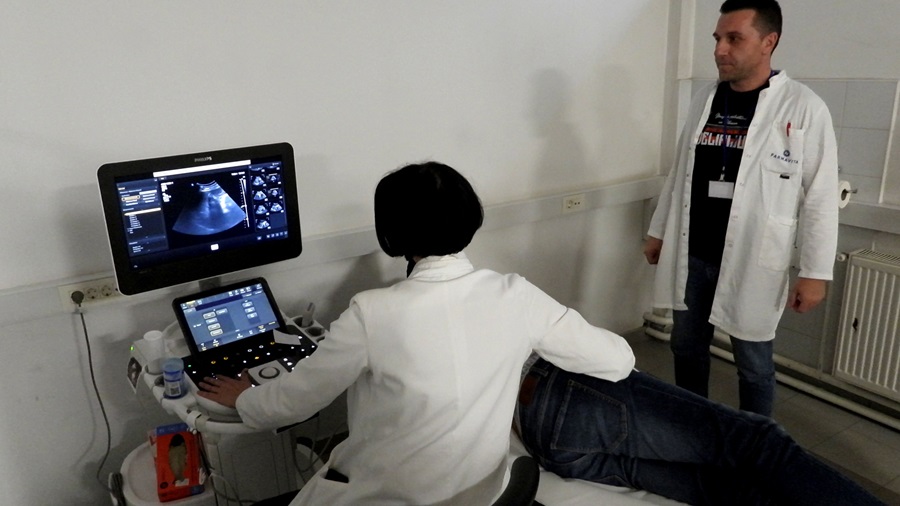

– Okončali smo dva ciklusa koji su se sastojali u kontinuiranoj edukaciji od bazičnog i naprednog kursa. Sa današnjim danom su izeducirano 18 ljekara koji mogu da obavljaju samostalno ultrazvučne preglede abdomena, što je nama jako drago, jer to će biti najveći benefit pacijenata. Grupa kolega koje su završili prethodni napredni kurs rade već samostalno. Tako da će i kolege koji su danas završili kurs, nadam se, ubrzo početi samostalni rad, ističe dr. spec. radiolog Aida Vehabović, koja je predvodila tim edukatora, u kojem su bili i dr. Lejla Šaranović Čečo i dr. Alen Okanović.

Foto: dr. Aida Vehabović

Edukacijom se stvara veći broj educiranih doktora koji mogu samostalno i sigurno raditi ultrazvučne preglede, što direktno povećava dostupnost dijagnostičkih pretraga pacijentima. Što više obučenih ljekara imamo, to su liste čekanja kraće, a građani brže dolaze do pregleda, posebno kada je riječ o preventivnim kontrolama. Organizatori su zahvalili kompaniji Farmavita na podršci realizaciji edukacije, kao i Philipsu, koji je ustupio dodatne uređaje za edukaciju.

Uz Kantonalnu bolnicu Zenica u projektu su učestvovali Ministarstvo zdravstva i Ljekarska komora ZDK, kompanije Farmavita i Philips, te Institut za zdravlje i sigurnost hrane Zenica. Dio vizije kontinuirane edukacije jeste jačanje zdravstvenog sistema u smislu dostupnosti ove dijagnostičke metode pacijentima u njihovim lokalnim zdravstvenim ustanovama. Prema podacima organizatora, certifikate su dobili doktori Alen Mahić, Sabina Bašić, Hana Torlak, Farisa Babić Šabanović, Mirel Čizmić, Dževad Velagić, Dragan Radoš, Selmir Osmanbegović i Belmin Prasko.